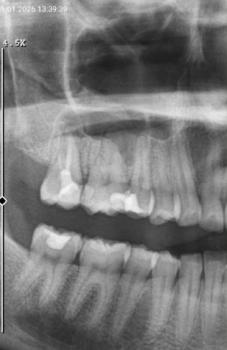

You brush, you floss, you see your dentist regularly — yet you still get cavities. If you live in an advanced country like the United States or Ireland, this can feel surprising, even unfair. Despite access to clean water, fluoridation, and modern dentistry, tooth decay remains one of the most common chronic diseases worldwide. Why? Because cavities are a complex interplay of diet, genetics, saliva, oral bacteria, and often, subtle habits we overlook.